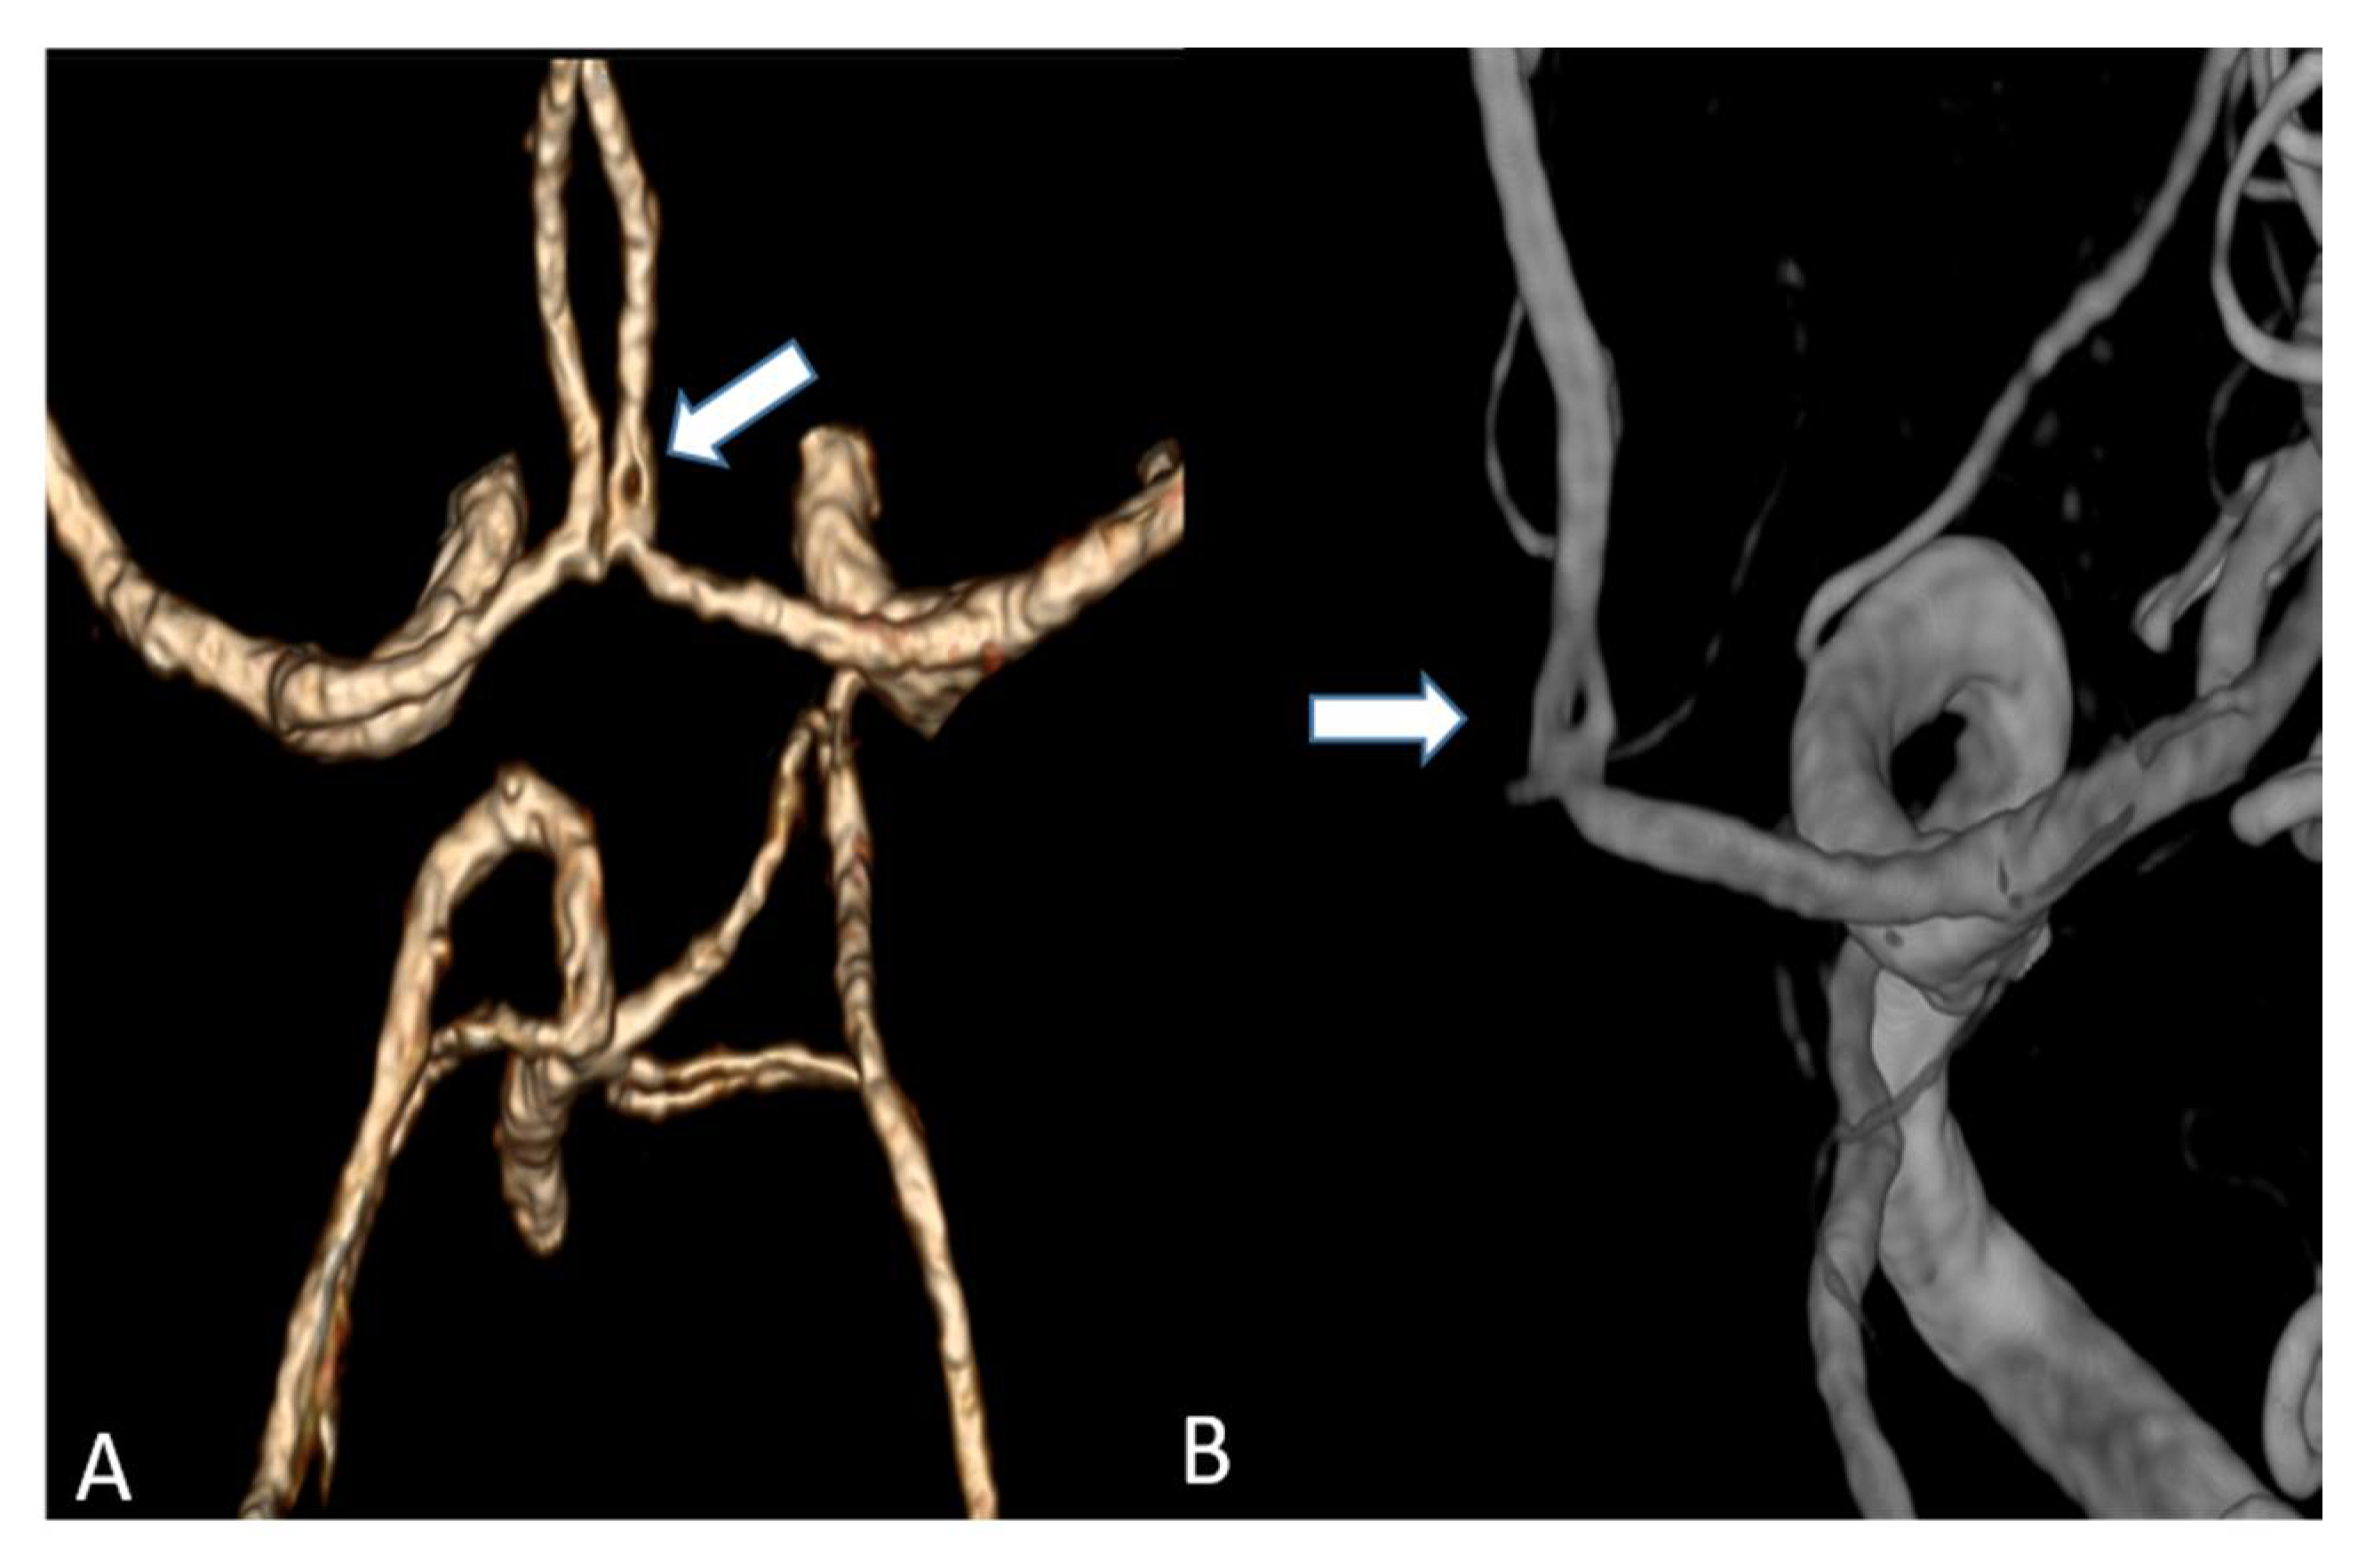

We were able to show that excellent image qualities were generated even though radiation exposure could be kept at explicitly moderate levels [10]. In addition, the occurrence of Hounsfield artefacts that frequently hinder the assessment of the vertebrobasilar system and the brainstem were also considerably low, enabling an advanced image interpretability. Both quantitative and qualitative evaluation of the UHR-CTAs confirmed our hypothesis of a highly remarkable improvement in image quality and spatial resolution. In particular, a high vascular contrast and a distinctly defined demarcation of the extracranial as well as the intracranial vessels could be demonstrated. It is noteworthy that even the smallest perforating arteries (e.g., LSA, as shown in Figure 3) vascularizing the deep brain structures become diagnostically accessible by UHR-CTA, which is generally not the case when using conventional CTA.

Studies on coronary artery and small visceral artery CTAs [11,12] have recently shown that the UHR-CT system is highly suitable for a significant improvement in image quality, SNR, CNR and an enhanced vascular imaging. Our investigation, which to our best knowledge represents the first study to evaluate image quality, contrast and delineation of the supra-aortic vessels and the small perforating arteries, confirms the excellent qualification of the UHR-CTA as a diagnostic tool in radiological and vascular imaging. Hence, the use of UHR-CTA will be of high value in various clinical settings, especially when a high resolution is inevitable for an accurate diagnosis and optimized patient care. In detail, advances in the diagnosis of aneurysms and steno-occlusive diseases may be reached, especially when looking at aneurysm configuration, and peculiarities or irregularities of the of aneurysm wall. UHR diagnostics may additionally improve pre-invasive planning of subsequent digital subtraction angiographies and interventions, enabling earlier and more individualized treatment decisions. An additional benefit will arise from a substantially reduced radiation exposure due to the omission or the time reduction in follow-up examinations.

Figure 5. (A) Volume rendering of an anterior cerebral artery fenestration acquired by an UHR-CT (B) Three-dimensional (3D) digital subtraction angiography (DSA) to confirm arterial fenestration in (A), which is often not detected by normal resolution CTAs.